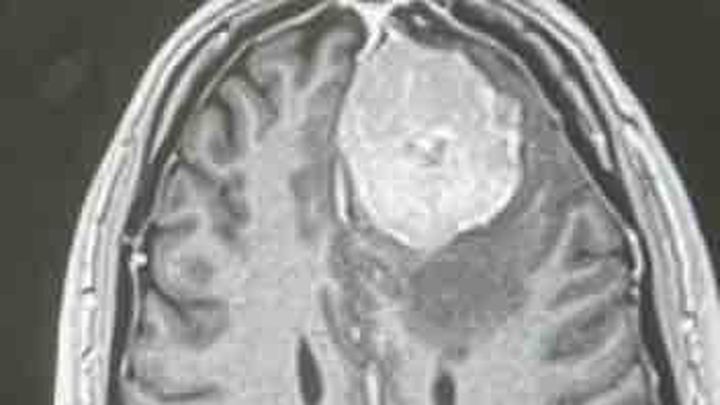

They advised that the tumor resection was successful and that the biopsy results came back as a WHO grade 2 atypical tumor.

The chances of it reforming is why they will be monitoring by MRI.

As part of my ongoing care, I have met with my medical team to establish a long-term monitoring plan. The tumor resection was successful, and biopsy results confirmed a WHO grade 2 atypical tumor. Since there is a risk of recurrence, I will continue to be monitored closely with regular MRIs over the next 1–2 years. I will also remain on anti-seizure medication for at least the next year.